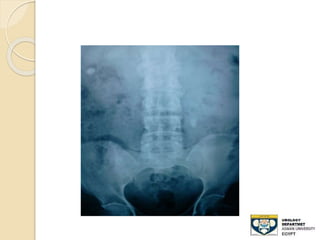

KUB film

 - Advantages:

◦ 80-90% of stones are radio-opaque

◦ Minimal radiation

 Disadvantages:

◦ Radiolucent stone

◦ Easy to miss mid-ureteral stones over the

sacrum

◦ Bowel gas can obscure its efficacy

◦ Cannot differentiate , Stones,Calcified LN

,

◦ Sensitivity: 50-70%